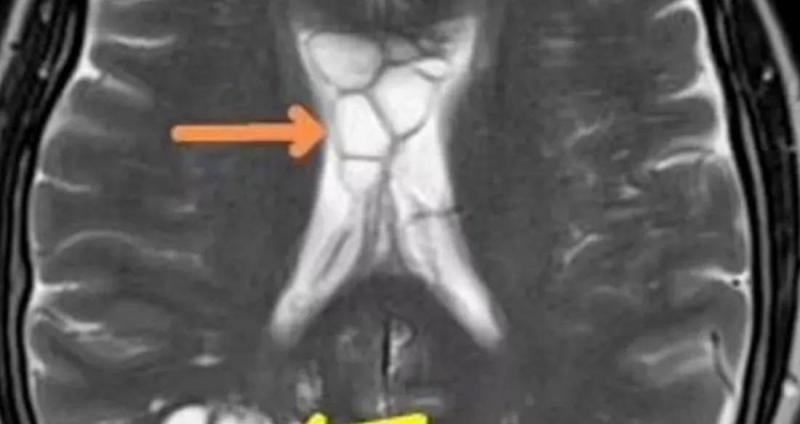

An American man who suffered from chronic headaches for months discovered that the cause was a parasite in his brain. After consulting with doctors, examinations revealed multiple cysts in his brain along with swelling, and experts confirmed that the cause was a tapeworm that had laid eggs in his brain. Doctors believe the parasite entered his body after he consumed undercooked food, subsequently migrating from the intestines to the brain via the bloodstream. Individuals can contract neurocysticercosis in various ways, including swallowing eggs through the consumption of improperly cooked or inadequately washed foods. The symptoms and severity of the condition depend on the number of cysts present in the brain, but confusion, balance issues, and excess fluid in the brain are some of the main signs of the condition.